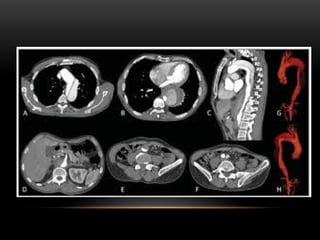

TC MULTICORTES

 Possuem mais de uma fileira de detectores.

 Para cada volta completa do tubo de raios x, mais de

um corte é gerado simultaneamente.

 Podem possuir 2,4,8,16,32,64,128,256 e até 320

canais.

 Há um modelo, que conta com dois tubos de raios x e

dois detectores de 64 canais cada.

 É possível até mensurar a passagem do sangue pelos

tecidos (estudo da perfusão).

TC MULTICORTES  Possuemmais de uma fileira de detectores.  Para cada volta completa do tubo de raios x, mais de um corte é gerado simultaneamente.  Podem possuir 2,4,8,16,32,64,128,256 e até 320 canais.  Há um modelo, que conta com dois tubos de raios x e dois detectores de 64 canais cada.  É possível até mensurar a passagem do sangue pelos tecidos (estudo da perfusão).